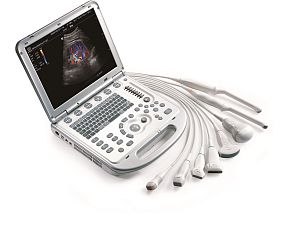

- Мультипортовый адаптер упрощает смену датчиков

Система Sparq оснащена мультипортовым адаптером, позволяющим одновременно подключить к системе до трех датчиков и легко переключаться между ними во время исследования.

Датчики

- C9-4v

Интраоперационные

- L15-7io

Конвексные

- C5-1 PureWave

- С6-2

Линейные

- L12-4

Матричные

- X7-2

Секторные

- S4-2